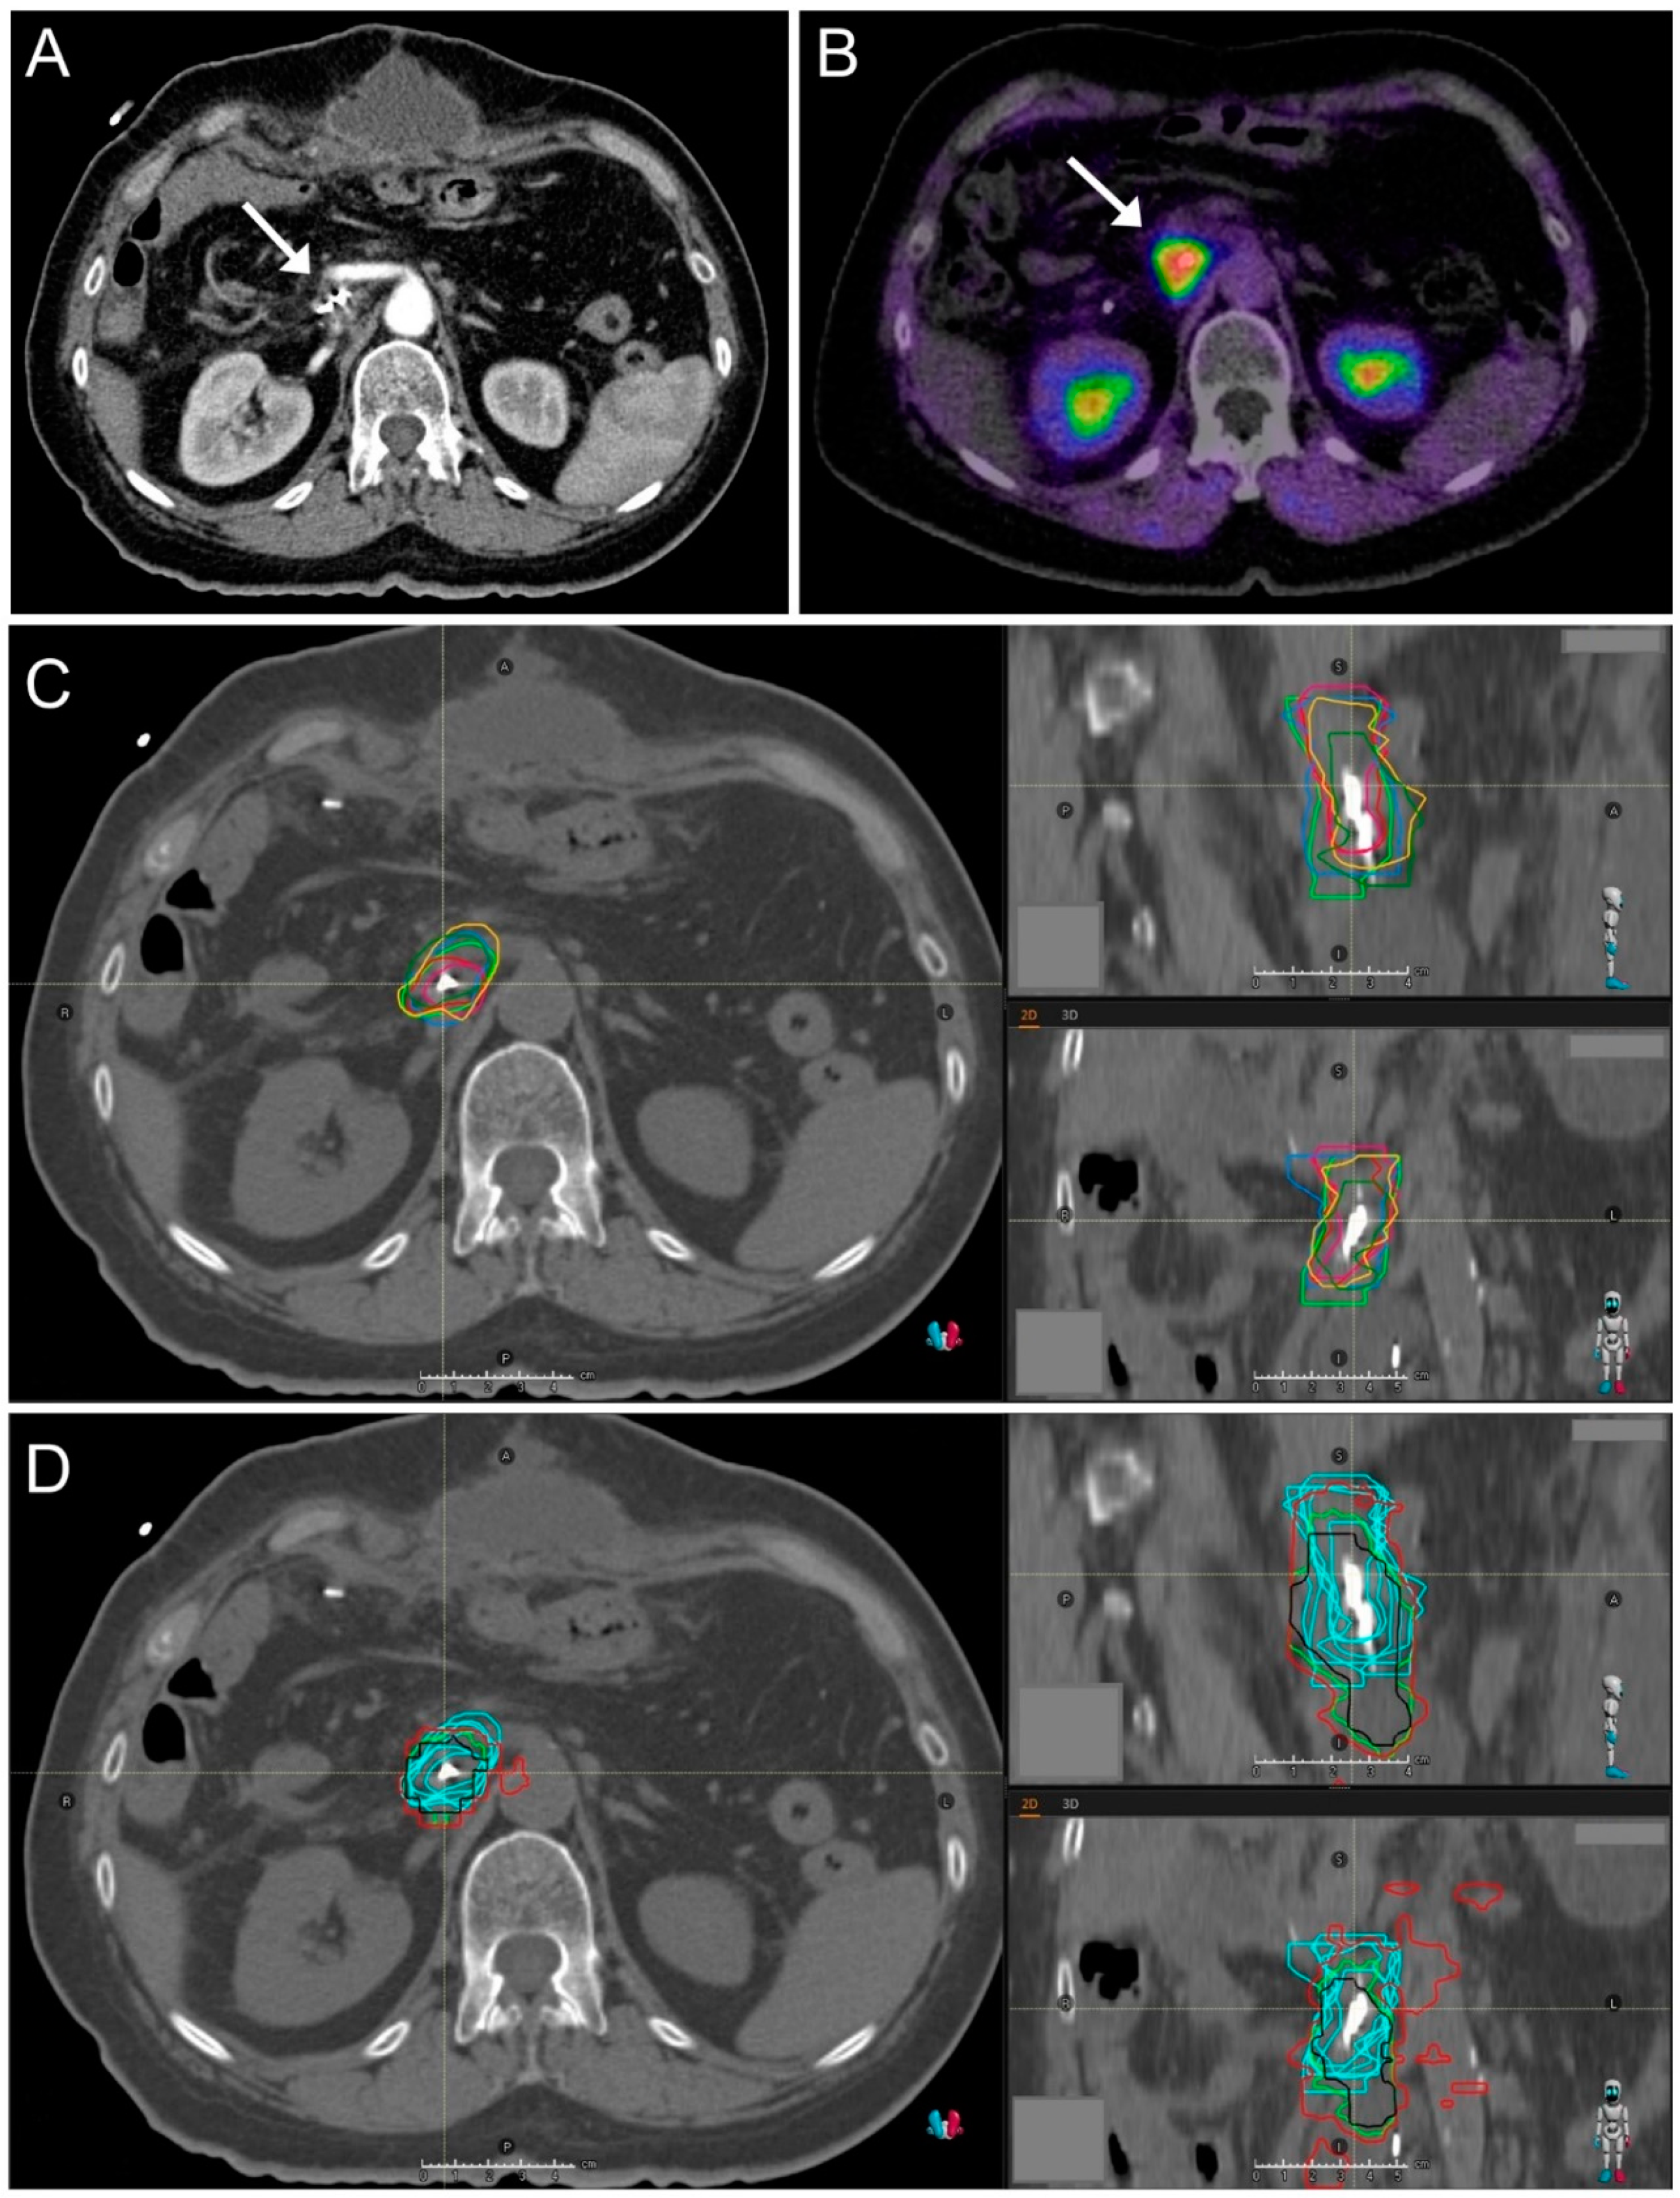

2.1. CT Imaging and Target Volume Definition by Radiation Oncologists

2.2. FAPI-PET/CT Imaging

2.3. Automated Target Volume Definition in FAPI-PET/CT-Scans

2.4. Image Registration

2.5. Interobserver Variability